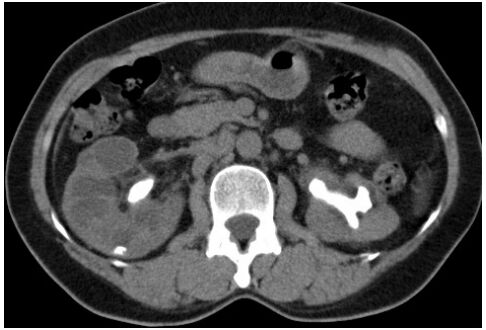

34.關於下圖之電腦斷層檢查,下列敘述何者最適當?(A)此圖為施打顯影劑後之電腦斷層影像,顯影劑已進入腎臟集尿系統 (B)此圖為施打顯影劑後之電腦斷層影像,顯影劑已進入腎臟實質 (C)此圖為未施打顯影劑之電腦斷層影像 (D)此圖為施打顯影劑後之電腦斷層影像,顯影劑已進入腎動脈